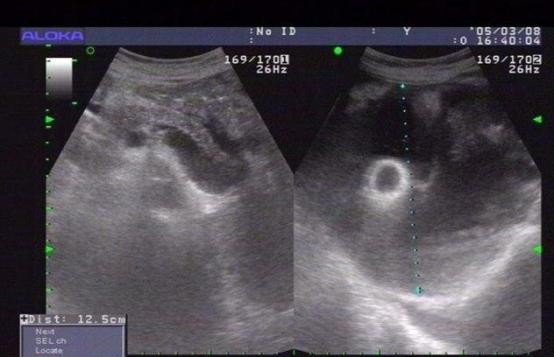

肝腹水是一種嚴重的疾病,通常是由于肝臟功能受損導致體內液體潴留而引起的。在疾病的早期階段,患者可能會通過藥物治療和飲食控制來緩解癥狀。然而,當肝腹水進展到晚期時,病情可...